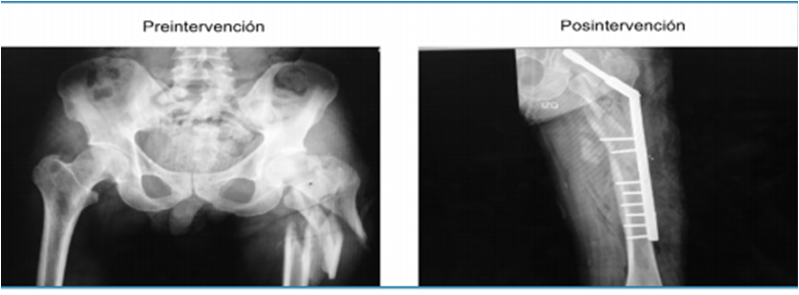

· 6 pacientes con fracturas pertrocantéricas, una de ellas expuesta GIIIB (Fig. 1) manejada inicialmente con limpiezas quirúrgicas y sistema VAC, se utilizó osteosíntesis con DHS en todas, y uso de aloinjerto de chip esponjosa en 3 pacientes 30 cc y en 2 pacientes 60 cc.

· 3 pacientes con fracturas de tercio distal de fémur supraintercondíleas con gran defecto óseo, para las cuales se utilizó placa condilar bloqueada en todas, se usó en un paciente 30 cc de aloinjerto de chip de esponjosa y en 2 aloinjerto de 60 cc de chip esponjosa (Fig. 2 y 3).